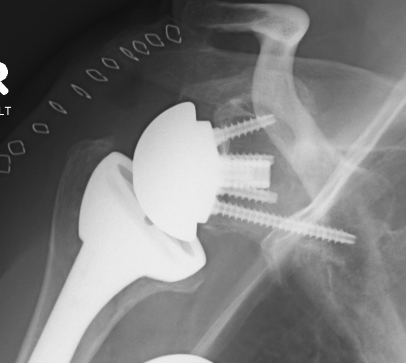

Centering guide wire passed

Depuy Synthes Delta Xtend

Center of inferior circle of glenoid

- metaglene needs to be positioned low to prevent inferior impingement and dislocation

- wire needs to angle perpendicular or slightly inferior / avoid superior tilt

- should exit scapula anteriorly about 3cm medial to glenoid

- ensure inferior screw will be in inferior good bone

- ream cartilage to subchondral bone

Metaglene / baseplate fixation

Screws as long as possible

- inferior screw - long into scapular pillar

- superior screw - aim for coracoid

- anterior / posterior screws - convergent / divergent

Depuy Synthes Delta Xtend

Glenosphere

Typically lateralized / slight inferior overhang